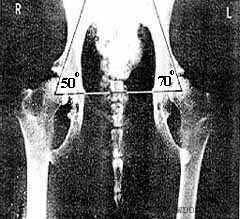

1. Угол Норберга (кранио-ацетабулярный)

измеряется между прямой линией,

соединяющей геометрические центры

головок бедра и линии, проведенной от

центра головки вдоль передне-наружного

края суставной впадины. Разметка

рентгенограммы производится,

согласно методике, специальным

планшет-транспортиром, с последующим

измерением угла обычным

транспортиром.